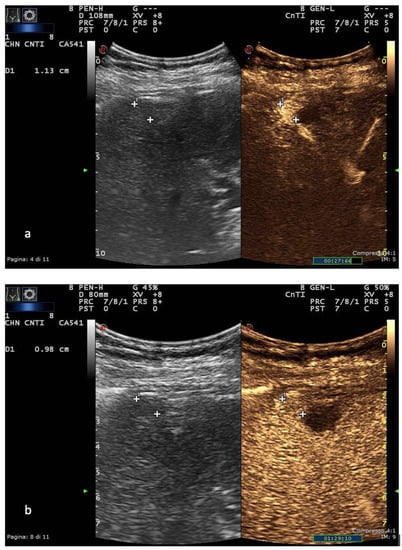

In Europe, CEUS is usually performed with SonoVue® (Bracco, Milan, Italy), which is not uptaken by Kupffer cells and hence produces an arterial, portal-venous and late phase [38]. The hallmark of HCC on CEUS using SonoVue® is a homogeneous and intense arterial phase hyper-enhancement (APHE) with mild wash-out starting >60 s after injection [39] (Figure 1).

US and CEUS surveillance examination in a patient with HBV-related cirrhosis. Baseline images detect the presence of a centimetric subcapsular hypoechoic nodule. After administration of USCA, the lesion shows arterial hyperenhancement (a) with a mild portal-venous wash-out (b).

The timing and degree of wash-out are important for the characterization of HCC, which typically shows milder hypo-enhancement compared to metastasis and cholangiocarcinoma. Nodules measuring >5 cm may show heterogeneous enhancement due to necrosis. Both the size and the degree of differentiation affect the enhancement pattern of HCC [40]. Wash-out is less often seen in HCC nodules <2 cm but is more frequent in HCC with poorer grades of differentiation [41].